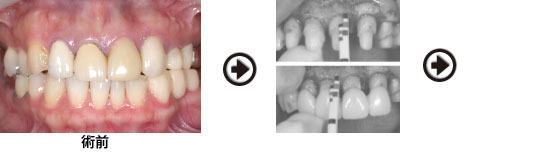

オールセラミック クラウン ブリッジ 症例

歯槽堤(歯肉)の陥凹を防ぐ為、抜歯部位に骨補填剤と軟組織を移植しました。

ファイバーコア(土台)を製作し、歯肉の成熟を待って、型取りを行います。